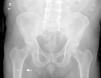

Most cases of sciatica are caused by compression of lumbar nerve roots, although some originate from extraradicular structures, such as in ischiofemoral impingement syndrome. We present the case of a 64-year-old man with a 10-year history of right-sided sciatic pain occurring only while seated. He underwent several lumbar surgeries for spinal stenosis (L4-L5, then L3-L4, and later L5-S1 with fusion to S1), as well as multiple infiltrations and pulsed radiofrequency, without improvement. Neurophysiological and imaging studies showed no significant compression, except for oedema at the ischial insertion of the quadratus femoris muscle. A diagnostic local anaesthetic infiltration temporarily resolved the pain, confirming ischiofemoral impingement syndrome. He was treated with osteotomy of the lesser trochanter, achieving complete pain resolution and functional recovery. This case highlights the importance of considering extraradicular causes in patients with persistent sciatic pain after spinal surgery.